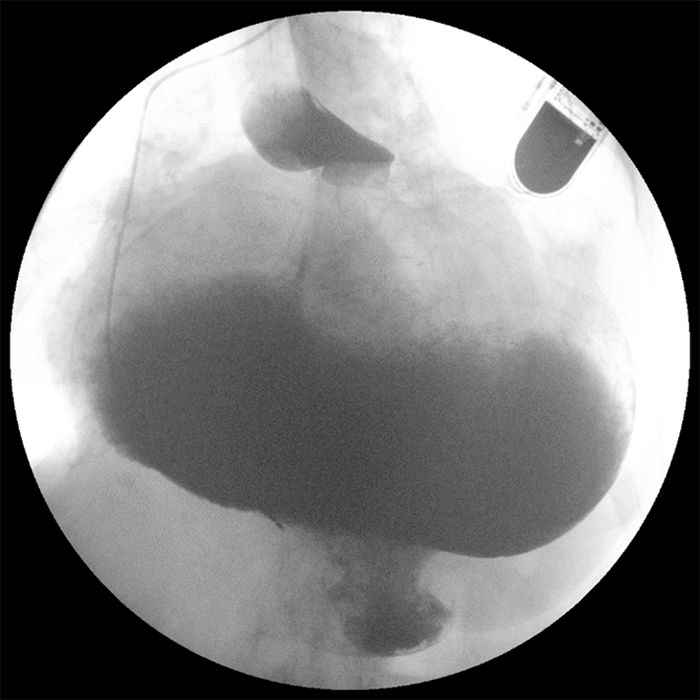

Computed tomography (CT) from outside facility performed earlier in the week revealed gastric outlet obstruction (GOO) caused by a massive type III PEH (Figure 1–4). She was subsequently discharged from this facility as she did not want surgical intervention and opted for hospice care. She presented to the ED later that week for persistent pain. At this time, it was decided to obtain a barium swallow instead of the repeat CT, demonstrating an intrathoracic stomach with concern for underlying gastric volvulus (Figure 5). Due to worsening obstructive symptoms, pain, and evidence of gastric outlet obstruction with possible gastric volvulus, it was recommended she undergo surgical intervention that day.

Figure 1. CT coronal view demonstrating large intrathoracic PEH.

Figure 2. CT coronal view demonstrating large intrathoracic PEH.

Figure 3. CT transverse mid-chest view.

Figure 4. CT transverse abdominal view.